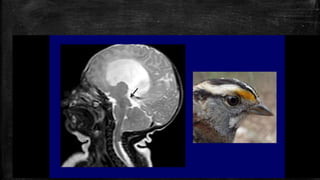

• #64 Ice-cream cone” sign of vestibular schwannoma. (a) Axial T1 SPGR post-contrast image shows an avidly enhancing mass (white solid arrow) extending from the CPA to the fundus of the IAC. (b) When large enough, vestibular schwannomas viewed in the axial plane resemble an “ice-cream cone” with the bulbous extension of tumour in the CPA resembling the ice-cream sitting upon a cone of tumour in the IAC.